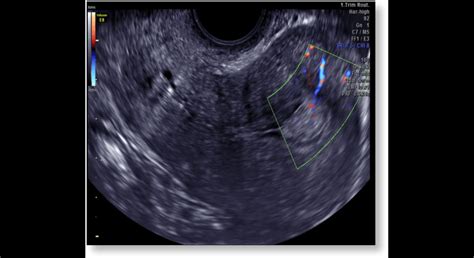

Gynekológ diagnostikuje hyperpláziu endometria maternice a určí jej typ po komplexnom vyšetrení, ktoré zahŕňa anamnézu, gynekologické vyšetrenie, ultrazvuk, hysteroskopiu a biopsiu (odber vzorky tkaniva na histologické vyšetrenie).